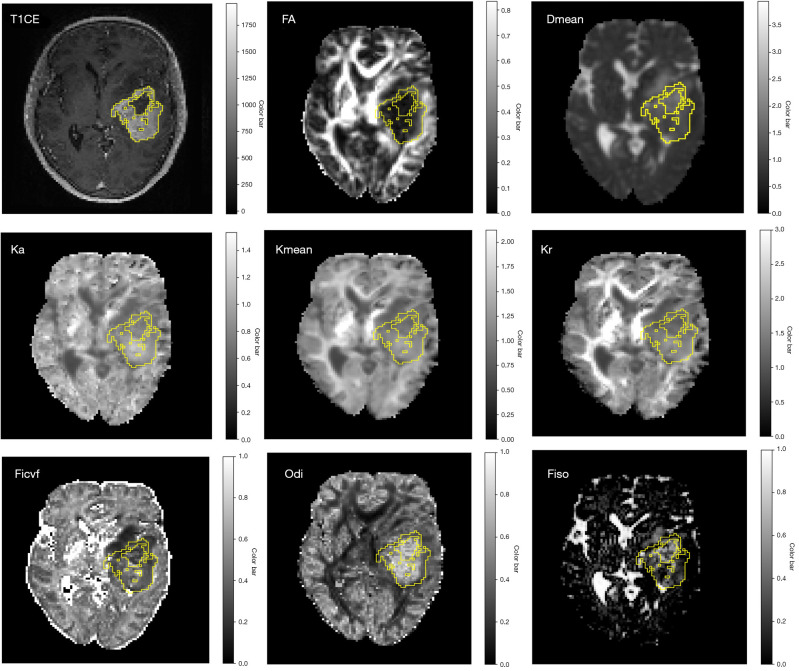

Background: Ki-67 labelling index (LI), a critical marker of tumor proliferation, is vital for grading adult-type diffuse gliomas and predicting patient survival. However, its accurate assessment currently relies on invasive biopsy or surgical resection. This makes it challenging to non-invasively predict Ki-67 LI and subsequent prognosis. Therefore, this study aimed to investigate whether histogram analysis of multi-parametric diffusion model metrics-specifically diffusion tensor imaging (DTI), diffusion kurtosis imaging (DKI), and neurite orientation dispersion and density imaging (NODDI)-could help predict Ki-67 LI in adult-type diffuse gliomas and further predict patient survival.

Methods: A total of 123 patients with diffuse gliomas who underwent preoperative bipolar spin-echo diffusion magnetic resonance imaging (MRI) were included. Diffusion metrics (DTI, DKI and NODDI) and their histogram features were extracted and used to develop a nomogram model in the training set (n=86), and the performance was verified in the test set (n=37). Area under the receiver operating characteristics curve of the nomogram model was calculated. The outcome cohort, including 123 patients, was used to evaluate the predictive value of the diffusion nomogram model for overall survival (OS). Cox proportion regression was performed to predict OS.